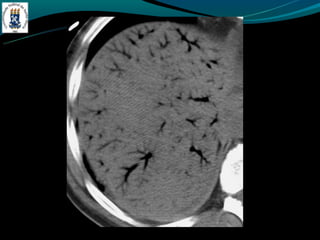

GÁS NO SISTEMA PORTA

-Mais frequentemente associado:

-Isquemia intestinal nos adultos

-Enterocolite necrosante nos RN

-Outras causas: colonoscopia recente, sonda de gastrostomia, DII,

diveticulite, abscesso abdominal…

GÁS NO SISTEMAPORTA -Mais frequentemente associado: -Isquemia intestinal nos adultos -Enterocolite necrosante nos RN -Outras causas: colonoscopia recente, sonda de gastrostomia, DII, diveticulite, abscesso abdominal…